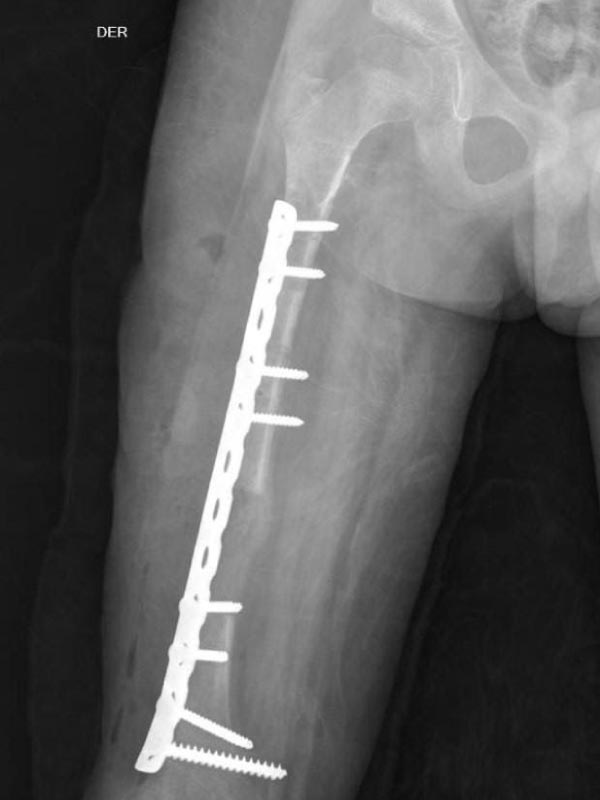

Caso No. 6 - Hemimelia tibial derecha

Preoperación

Posoperación 1

Hemimelia Tibial Derecha

Diagnóstico: Agenesia de peroné + Acortamiento de extremidad inferior derecha

Primera cirugía: Fijación externa Ilizarov para alargamiento femoral

Posoperación 2

Rehabilitación

Segunda cirugía: cambio a fijación interna (7cm de alargamiento)

Paciente rehabilitándose y aun pendiente el alargamiento de la tibia derecha